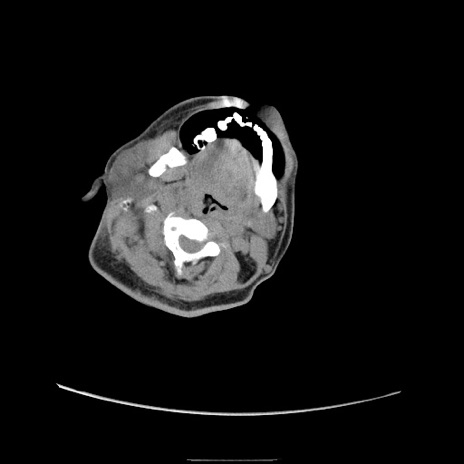

症例22(横断像)

【症例】50歳代男性

【主訴】腹痛

【現病歴】AVMからの被殻出血のため回復期リハ病棟入院中。 本日午後3時頃急に下腹部痛が出現した。

【既往歴】AVM、被殻出血、虫垂炎、高血圧

【身体所見】意識晴明、左半身不全麻痺、会話の理解は良好、36.5°C、腹部:膨隆、全体に板状硬、下腹部正中に圧痛点あり、反跳痛-、筋性防御不明、右下腹部にope scar

【データ】WBC 9400、CRP 0.06